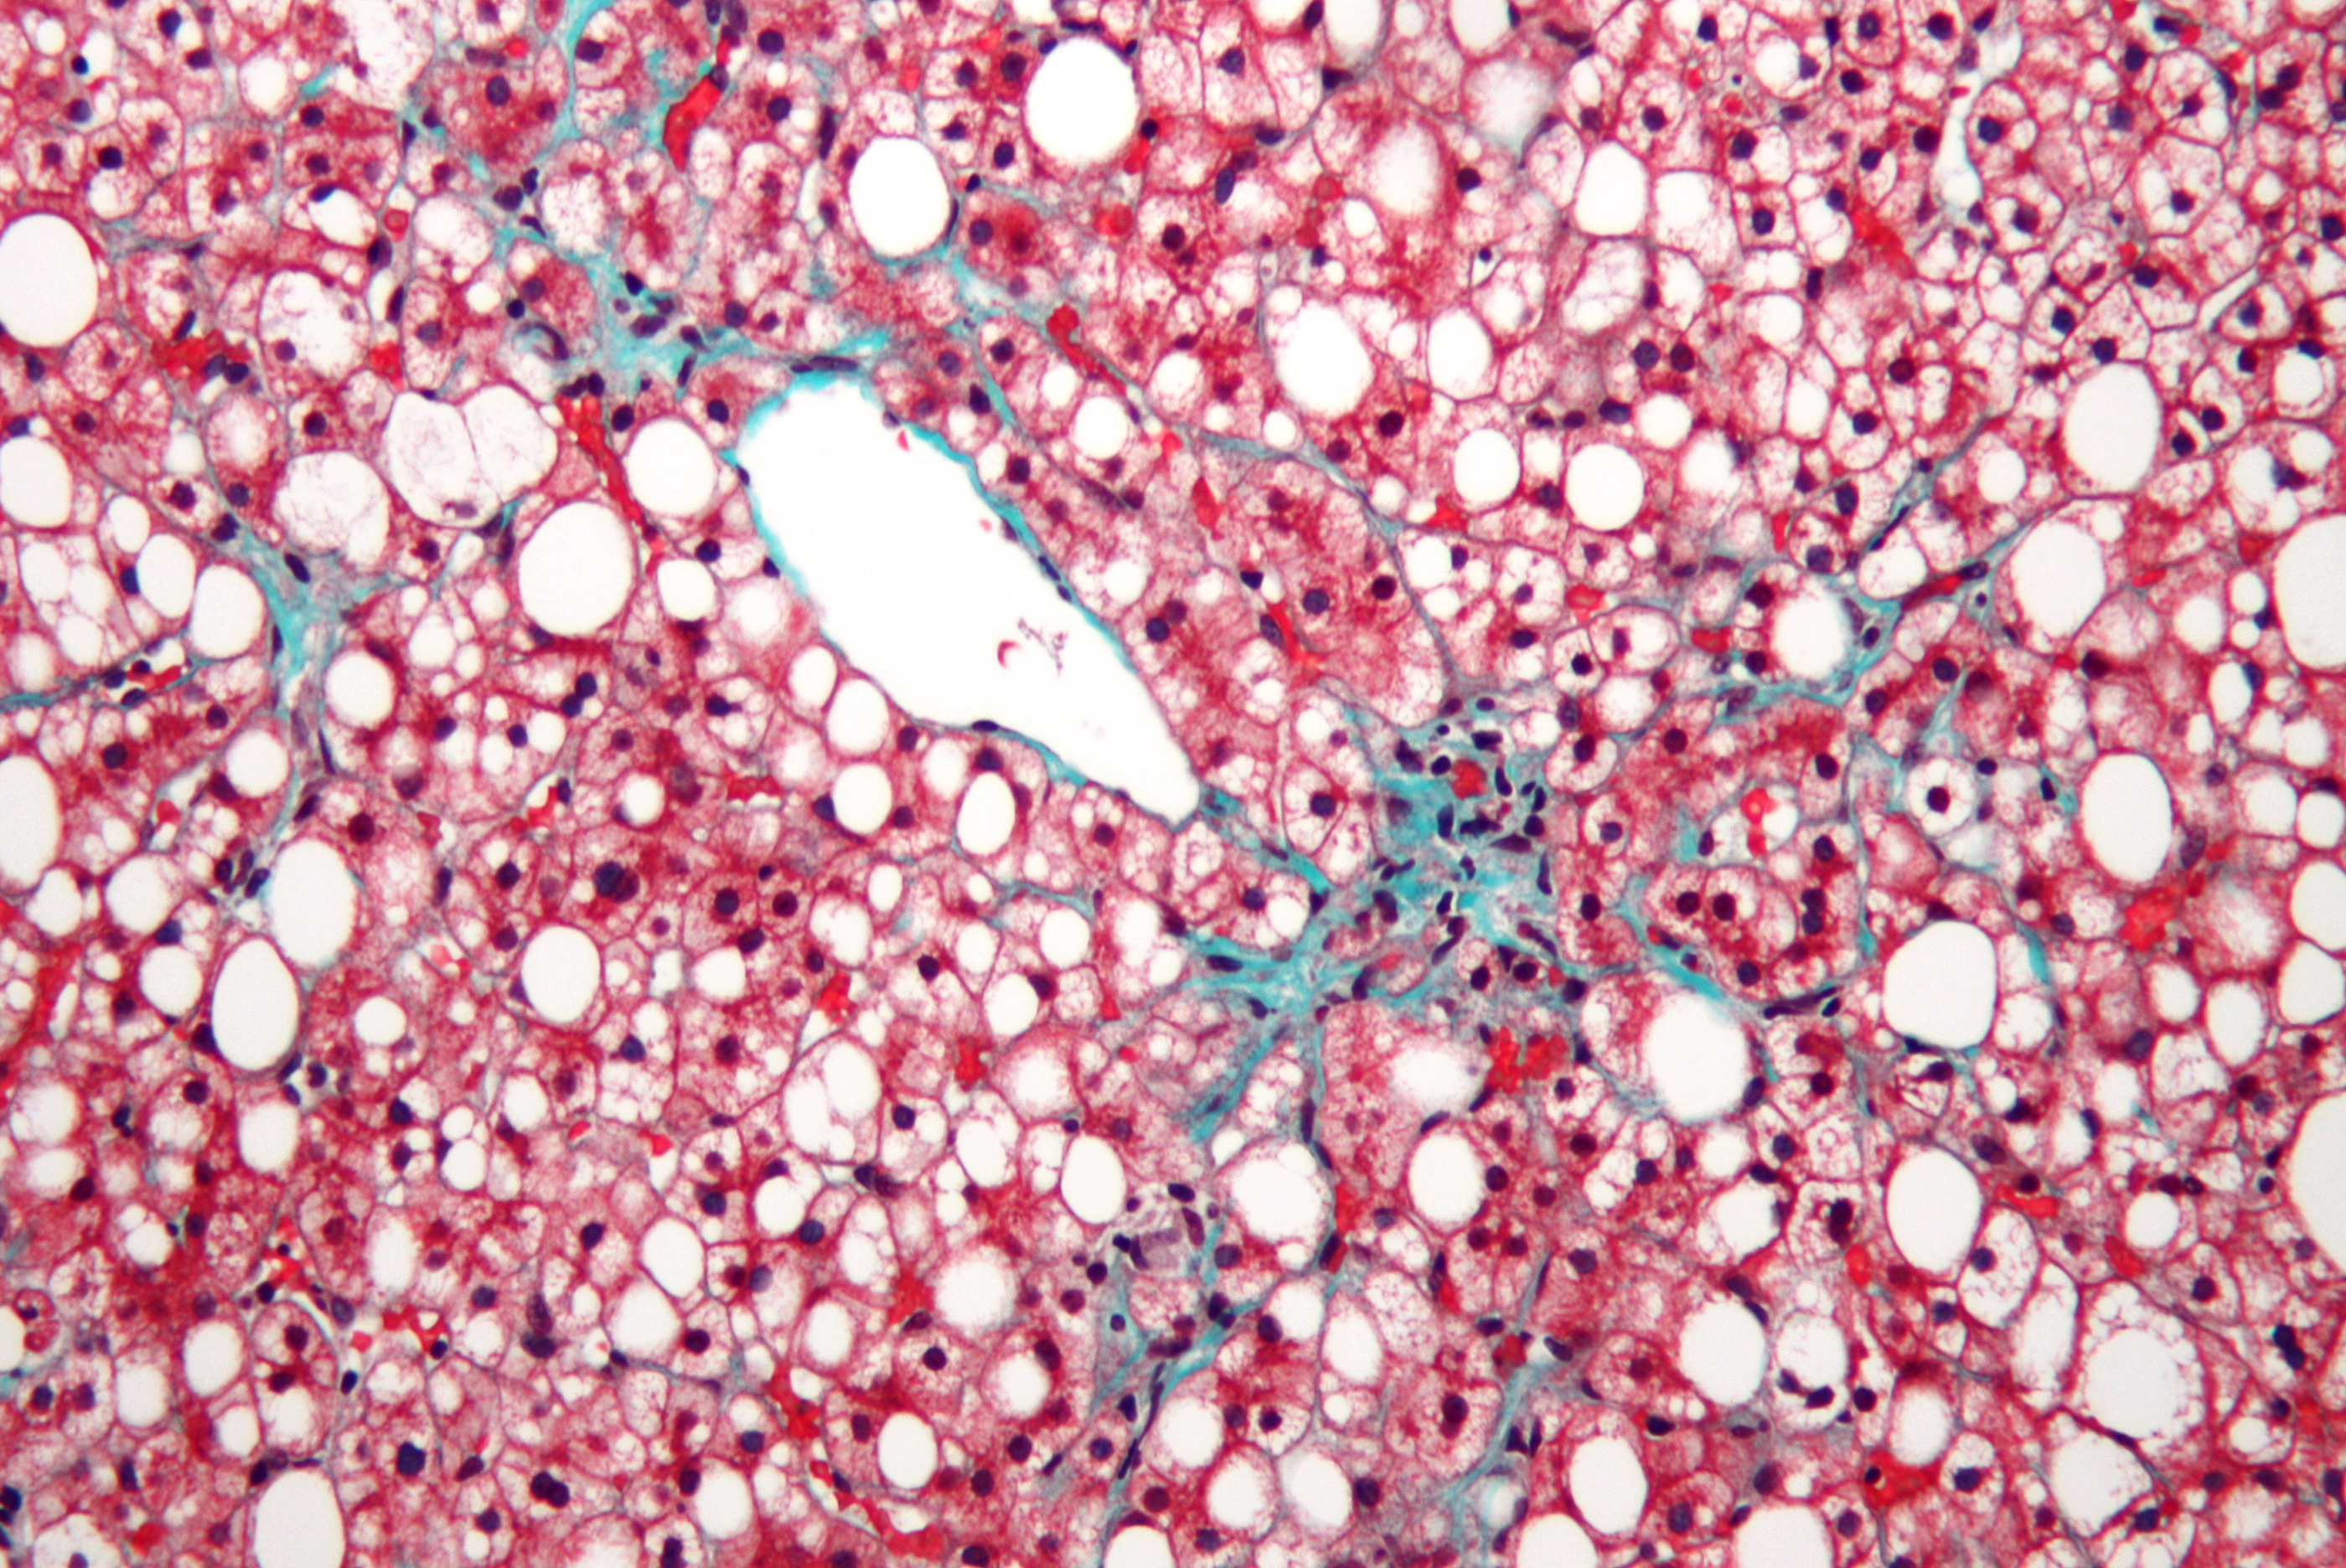

È il danno a due barriere dell'intestino, causato da una dieta ricca di grassi, a provocare lo sviluppo della steatoepatite non alcolica (NASH), malattia cronica del fegato che può portare alla cirrosi e insufficienza epatica. Lo hanno dimostrato i ricercatori guidati dall’Istituto Clinico Humanitas di Milano, il cui studio è pubblicato sul Journal of Hepatology.

Il nostro intestino è protetto da due barriere, una epiteliale esterna ed una vascolare, che impediscono ai batteri di passare nel sangue. Ma, come hanno dimostrato gli studiosi, un'alimentazione ricca di grassi altera la composizione del microbiota intestinale (cioè l'insieme dei batteri e microrganismi presenti) che, a sua volta, modifica la barriera vascolare con impatto sul fegato e sullo sviluppo della steatosi epatica non alcolica.

«Mettendo per la prima volta in correlazione l'intestino con il fegato, abbiamo dimostrato che un'alimentazione ricca di grassi induce un'alterazione del microbiota capace di danneggiare la barriera vascolare», spiega la coordinatrice dello studio, Maria Rescigno. Una volta aperta la barriera, alcuni batteri possono spostarsi dall'intestino al fegato, creando un'infiammazione che a lungo andare può provocare lo sviluppo della steatosi epatica non alcolica e, in seguito, della sindrome metabolica.

A soffrire delle malattie del fegato grasso sono almeno il 25% degli italiani, una percentuale che può arrivare al 50% nelle persone obese. Dalle analisi condotte nella ricerca, si è capito che quando la barriera è chiusa si riesce a bloccare lo sviluppo della malattia. Il più delle volte lo sviluppo della patologia si ha in pazienti con la sindrome metabolica (che poi dà origine a diabete di tipo 2 e obesità) e può essere legato ad una dieta con molti zuccheri e grassi.